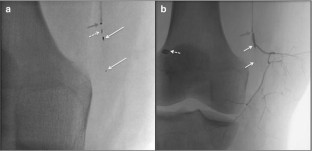

Fig. 1